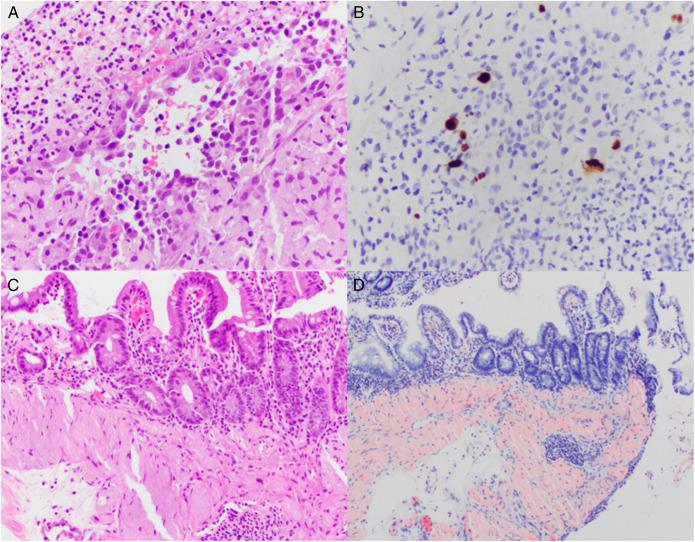

Concurrent Cytomegalovirus Colitis and Gastrointestinal Amyloidosis as Initial Presentation of Multiple Myeloma.

ACG Case Rep J. 2022 Oct 18;9(10):e00876. doi: 10.14309/crj.0000000000000876. eCollection 2022 Oct.